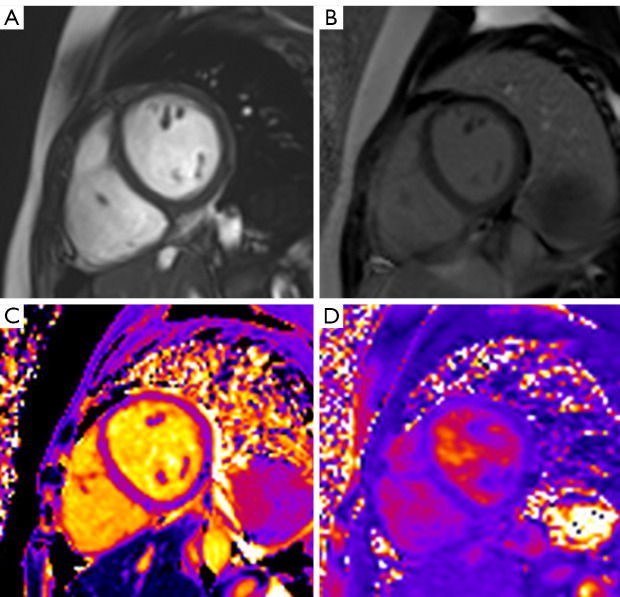

Methods: A total of 455 patients with KD were retrospectively recruited and divided into a non-CA involvement group (n=313) and a CA dilation-only group (n=142), with 16.1% (50/311) and 15.5% (22/142), respectively, undergoing cardiac magnetic resonance (CMR) examinations during recovery. Data regarding inflammatory markers, electrocardiography, and echocardiography were compared between the two groups both in the acute phase and during the recovery period. Kaplan-Meier analysis was performed to estimate the cumulative probability of the endpoints including coronary events, cardiac death, heart failure, and new-onset malignant arrhythmias.

Results: Baseline inflammatory markers, including white blood cell count (WBC) and C-reactive protein (CRP), were not significantly different between patients with KD and non-CA involvement and those with dilation only (median WBC: 14.1×109/L vs. 13.9×109/L, P=0.57; median CRP: 87.4 vs. 85.6 mg/L, P=0.73). In terms of echocardiography assessment at baseline, there were no significant differences between the non-CA involvement group and the dilation-only group in terms of left ventricular ejection fraction (67.8%±13.6% vs. 68.1%±10.3%; P=0.13) or fractional shortening (37.6%±5.3% vs. 35.4%±6.6%; P=0.25). For CMR assessment at recovery, the myocardial systolic function of patients with KD but non-CA involvement was not significantly different from that of patients with CA dilation only in terms of global radial strain (38.3%±18.7% vs. 39.9%±20.5%; P=0.20), global circumferential strain (-18.7%±6.8% vs. -18.3%±7.2%; P=0.38), and global longitudinal strain (-13.2%±3.7% vs. -13.4%±4.1%; P=0.17). The global native T1 value of patients with non-CA involvement was 1,296.5±74.1 msec, while that of patients with CA dilation only was 1,313.3±80.5 msec (P=0.21); there was also no significant difference in global T2 values between the two groups of patients (38.2±4.1 vs. 38.1±3.5 msec; P=0.53). Finally, at a median follow-up of 4.2 years, there was a favorable prognosis in both two groups of patients, with no patients reaching the endpoints.